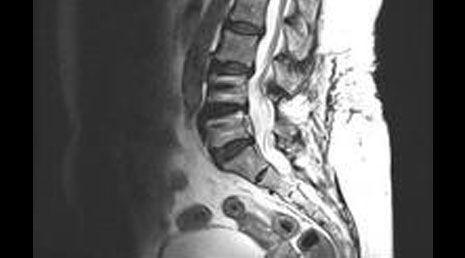

55. Spinal metastasis- adrenal